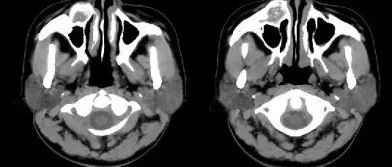

中年女性,右侧面部包块3年,请诊断!

医学影像  yxyx-app  医学影像APP,打造伴随医生快速成长的影像学习社区。与影像园(Xctmr.com)一起提供最全面的影像案例库、基础(解剖、病理、影像诊断)知识、影像技术及考题等,为医生提供最佳的医学影像参考。【所属科室】普外科【基本资料】患者,女,35岁【主诉】右侧面部包块3年【影像图片】【讨论问题】如何诊断?【医学影像APP用户讨论】评论:右侧上颌骨骨皮质显著变薄,呈膨胀性,病灶中心可见钙化,无骨膜反应及软组织肿胀。考虑右侧上颌骨良性病变,骨化性纤维瘤可能。...

医学影像APP 2022-08-15